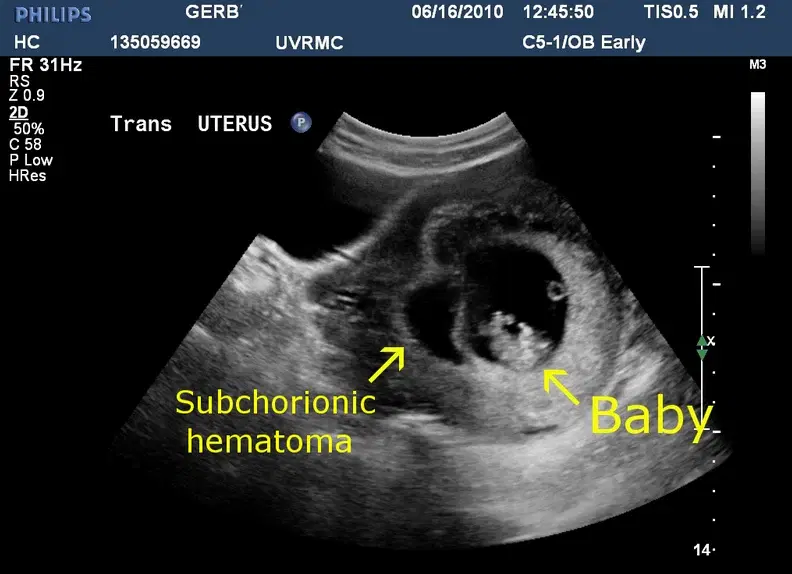

Educational Need / Practice Gap: Hemorrhage patterns are frequently confused with placental variants or mismeasured, impacting counseling and follow-up decisions.

● SCH definition and imaging features

● Location terms and how to describe

● Measurement approach and documentation